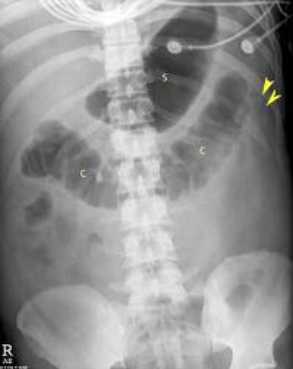

РЕНТГЕНОГРАФИЯ ПРИ ПАНКРЕАТИТЕ

Обзорная рентгенография органов брюшной полости в прямой проекции является частью первоначальной диагностической работы при острой боли в животе. Результаты на снимках неспецифичны, но позволяют заподозрить острый панкреатит. К наиболее часто встречающимся рентгенологическим признакам, связанным с острым панкреатитом, относятся:

- Наличие воздуха в дуоденальном изгибе

- Симптом очертания контура «песочных часов», что представляет из себя локальное расширение проксимальной петли тощей кишки в левом верхнем квандранте

- Симптом «урезанного толстого кишечника» представляет собой только наличие изображения восходящей и поперечой части толстого кишечника.

В обзоре 73 случаев к другим рентгенологическим признакам также относятся затушевывание краев почки, увеличение плотности мягких тканей эпигастральной области, увеличение расстояния от желудка до поперечной ободочной кишки, деформация желудка, кальцификаты поджелудочной железы и плевральный выпот (обычно слева). Примечательно, что у пациентов с острым панкреатитом рентгенологическая картина ОБП может быть абсолютно нормальной.

Обзорная рентгенография при остром панкреатите показывает отсутствие воздуха в нисходящей ободочной кишке — симптом «урезанной кишечника».